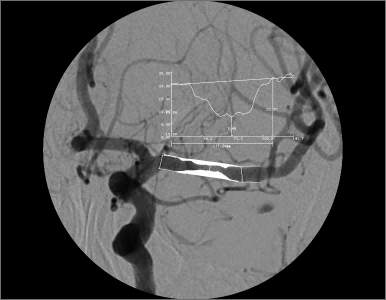

埃斯科核心实验室(IsCore image corelab) 是晓得(北京)商业发展有限公司旗下 的独立第三方核心实验室。由经验丰富的临床专家团队和影像放射专家团队组成, 致力于帮助临床医生和医疗领域的公司进行细致的、标准的、规范的影像管理和 判读。IsCore 影像实验室提供的影像判读数据已经为多家医疗机构的科研课题提 供数据支持,同时也已经协助国内外数个产品研发上市提供科学帮助。我们实验室的影像评价者均在国内顶尖专科医院接受过临床影像专业的系统学 习与规范培训,有多年的临床工作经验,以及强大的技术支持,能准确判读 MRI, HRMRI, DSA, OCT, CFD, VU 等影像,给出标准规范的报告结果,最低限度减少 了人为因素对试验结果的影响有助于科研成果产出和产品研发。